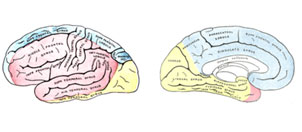

Зоны кровоснабжения:

Arteria cerebri anterior (синий цвет)

Arteria cerebri media (красный цвет)

Arteria cerebri posterior (жёлтый цвет)

Кровоснабжение головного мозга